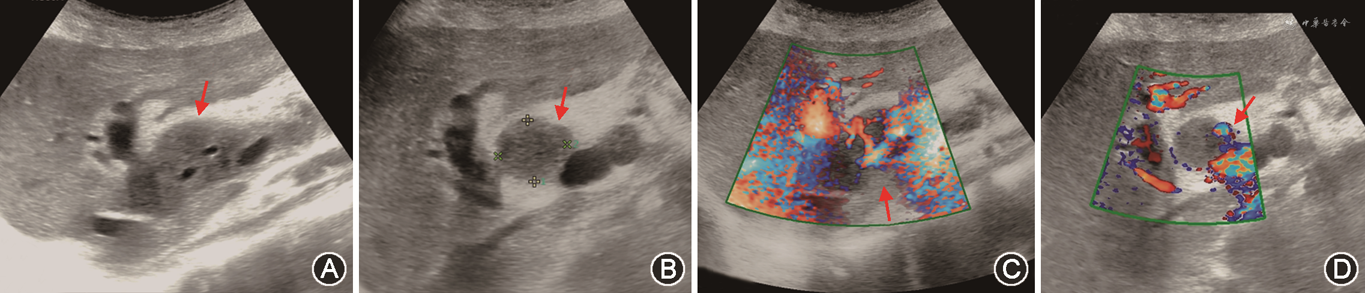

(2)PVS:移植肝PVS多发生在门静脉吻合口附近[73]。超声诊断PVS形态学依据是门静脉内径减少大于50%[74]。血流动力学依据包括:①门静脉吻合口处流速>125 cm/s[44];②门静脉吻合口处与之前正常段流速比值>3[74, 75]。以跨门静脉吻合口的两端流速差值>60 cm/s诊断门静脉显著狭窄,灵敏度可达100%,特异度为84%[76]。移植肝供受体门静脉内径不匹配时,CDFI检查门静脉有时可见湍流,应注意与PVS鉴别(图18)[77]。当门静脉吻合口处内径小于5 mm时,为防止移植肝预后不良,需及时进行介入手术或外科治疗[74]。